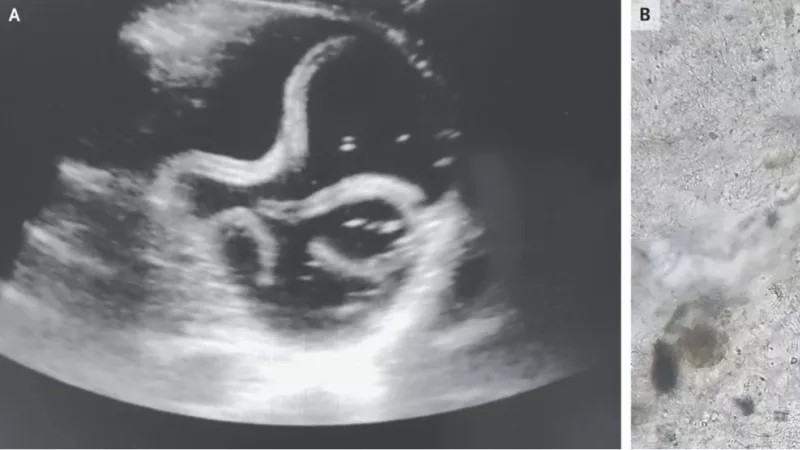

Bij het zien van een echofoto verwacht je natuurlijk een baby te zien. Alleen zijn er op deze plaat niet tien kleine vingers en tenen zichtbaar, maar slechts een langgerekte sliert. Juist, je kijkt naar de echo van een rondworm, Ascaris lumbricoides om precies te zijn. Dit is een parasiet die mens en dier kan infecteren.

De artsen besloten daarom een echo te maken van de onderste holle ader, een grote ader nabij de buik, van de man. Tijdens dit proces stuitten ze op een “buisvormige structuur die een krullende beweging maakte” in zijn maag. Een poepmonster wees uit dat de man een logé had: een rondworm die de patiënt hoogstwaarschijnlijk via besmet eten heeft binnengekregen.

Echo van de maag van de 20-jarige patiënt.